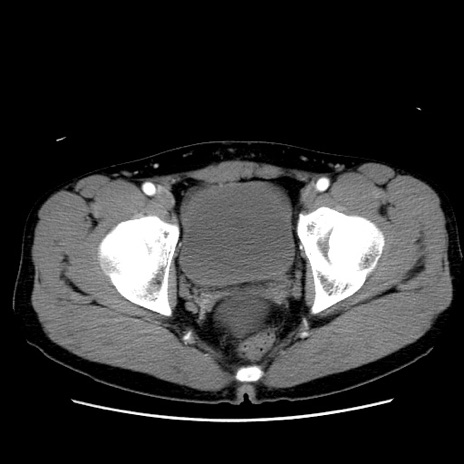

症例36(横断像)

【症例】20歳代 男性

【主訴】心窩部痛

【現病歴】今朝より上腹部痛あり。一旦軽快していたが再度出現したため救急要請。昨日夕に白身の魚を含む刺身を食べた。

【身体所見】BP 136/89mmHg、HR 74/min、BT 37.0℃、腹部:膨満、軟、心窩部に圧痛あり。反跳痛なし、筋性防御なし、腸雑音やや亢進あり。

【データ】WBC 17700、CRP 0.48